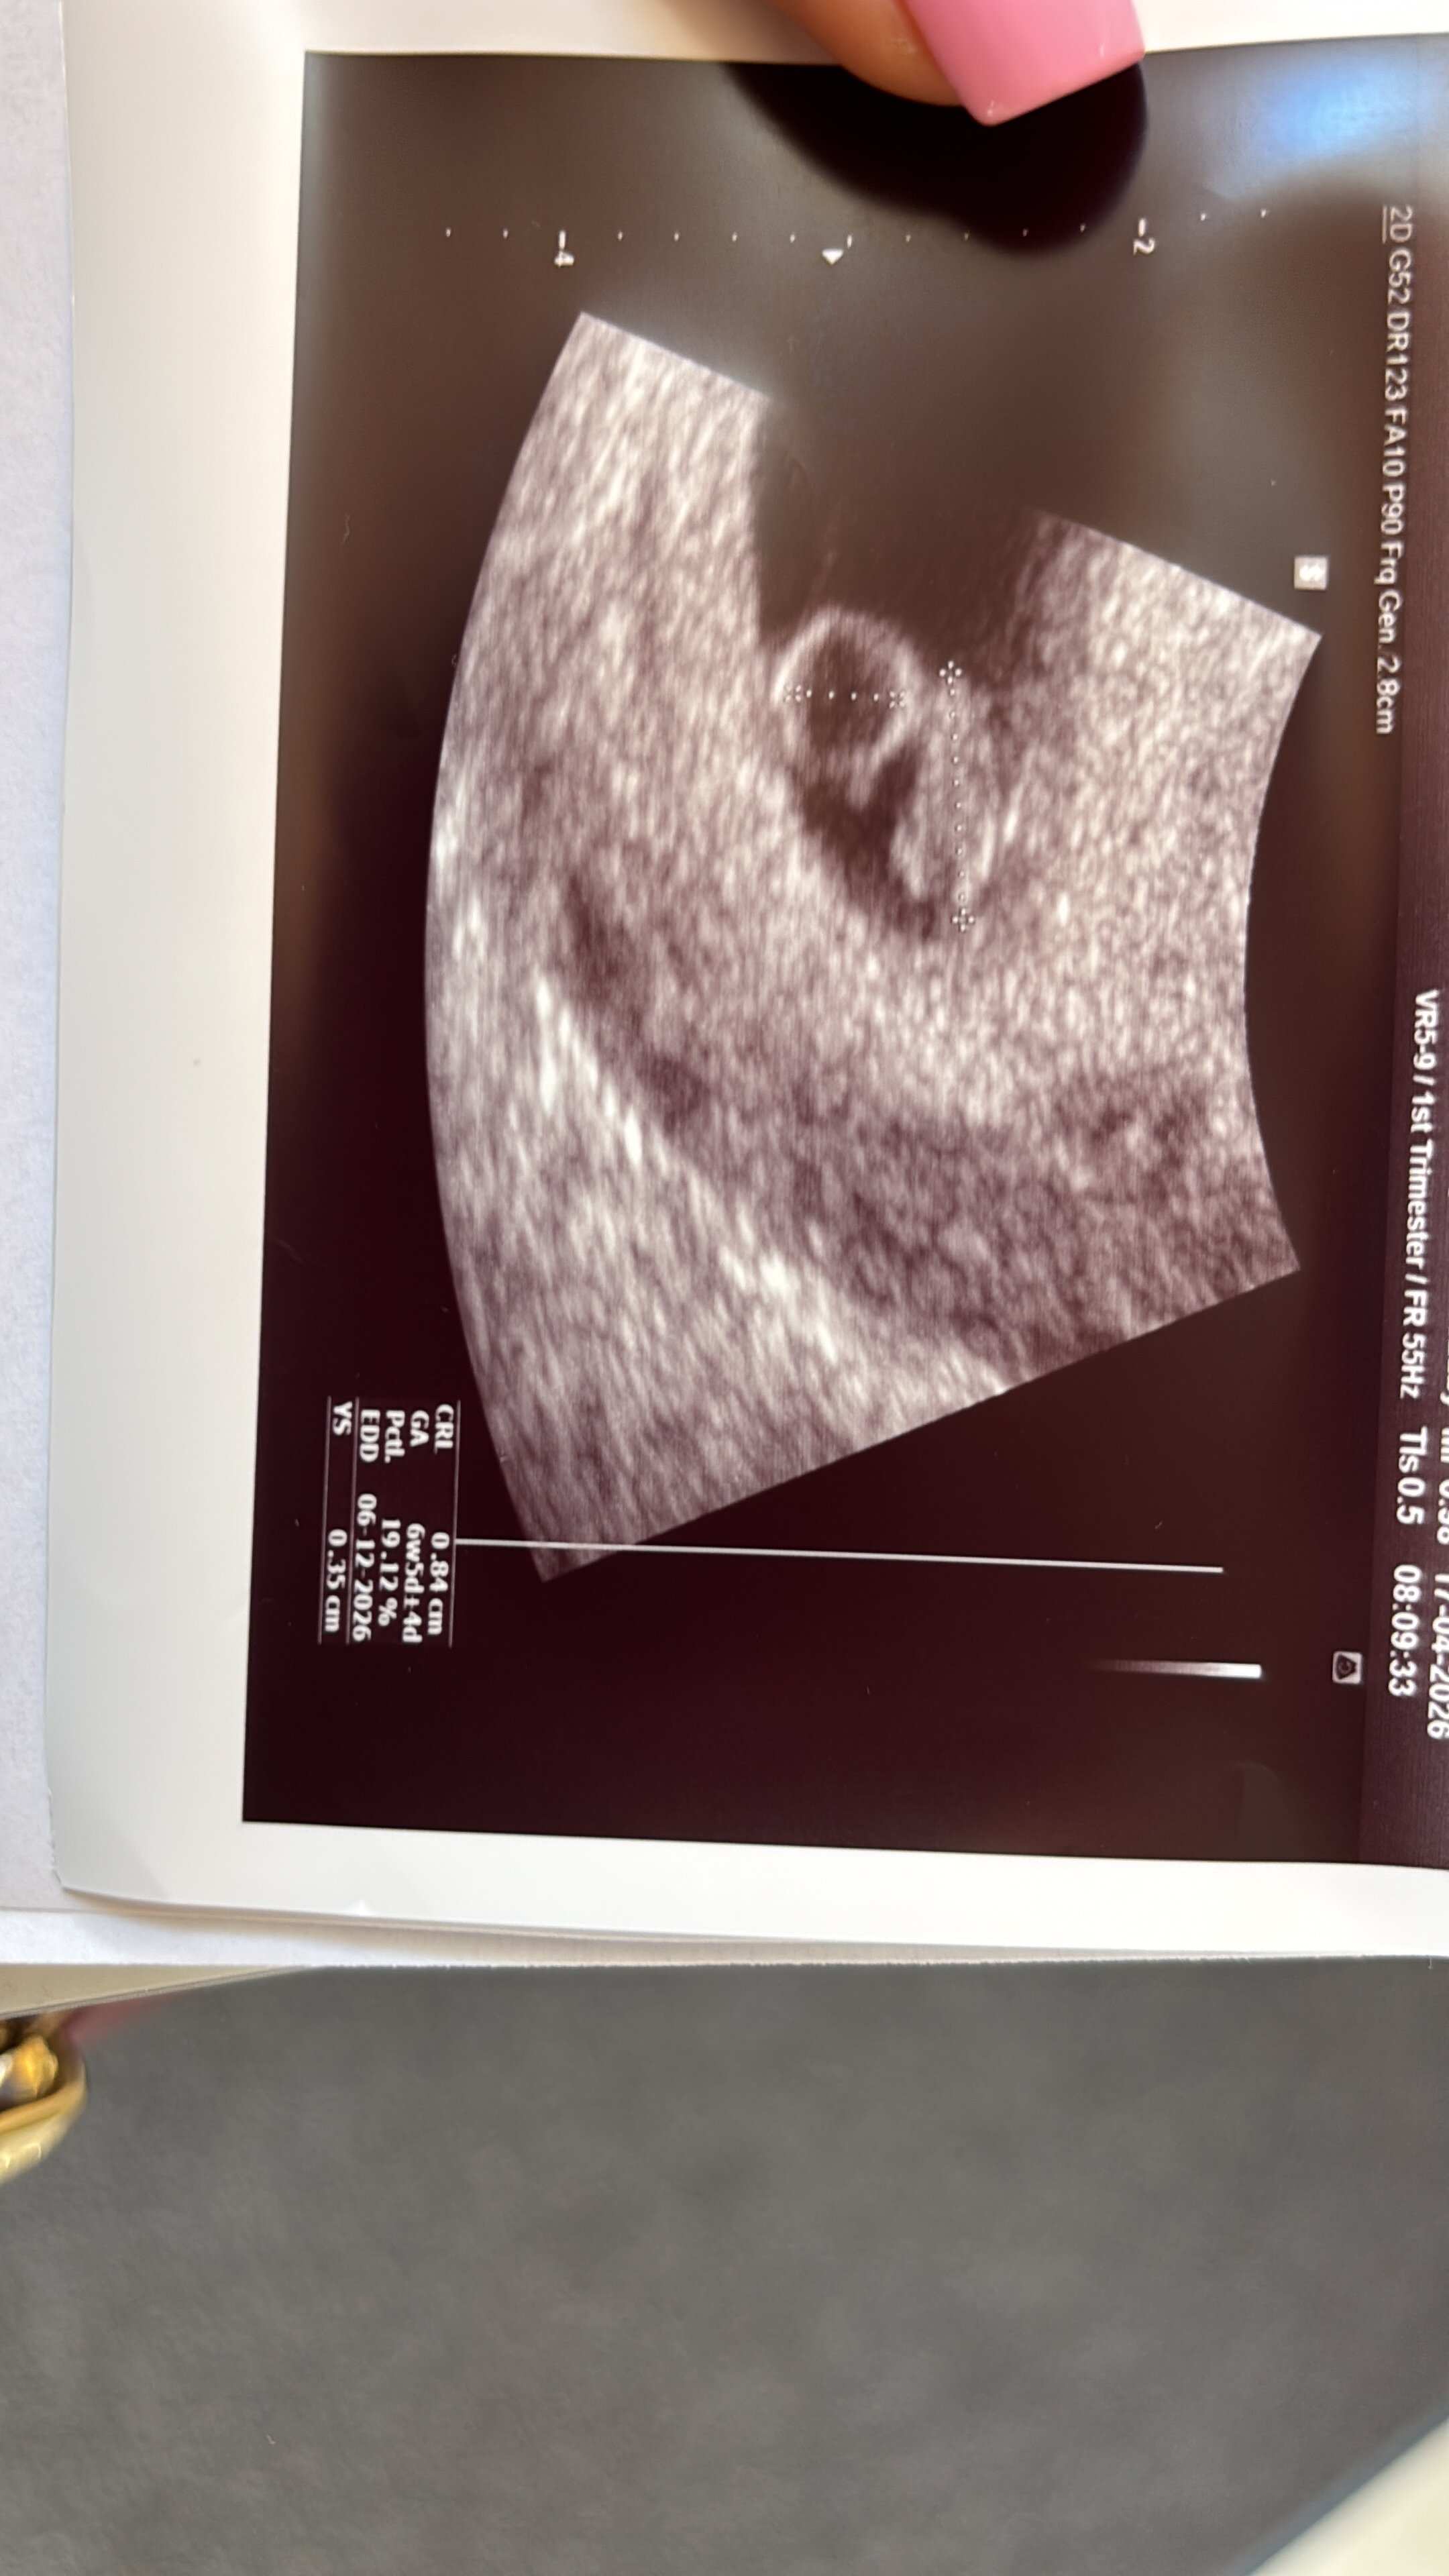

Cudownie!Jestem po wizycie! Bobasek jest, serduszko bije! Termin z USG 6.12![]()